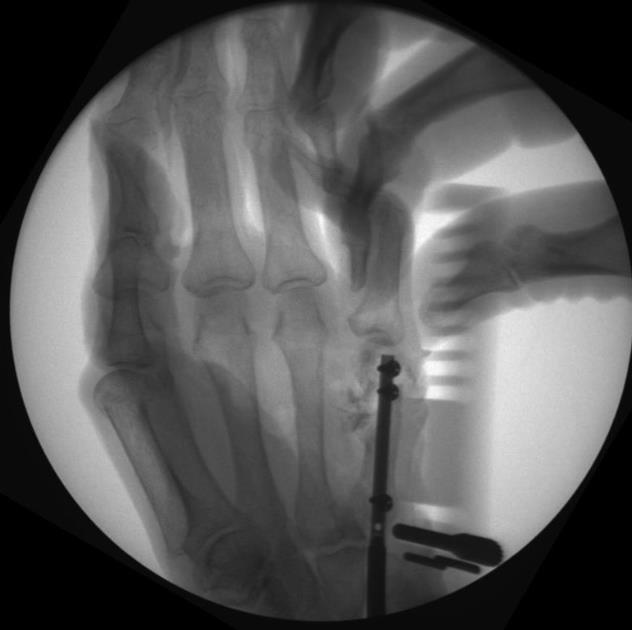

• confirm final reduction and implant position using fluoroscopy

• attach the phalanx coronal transfixion screw guide to the phalanx drill guide assembly with the provided screws

• ensure correct rotational alignment by fully flexing all digits simultaneously

• under fluoroscopy, advance a 1.1mm k-wire into the guide hole corresponding to the locking hand nail length

• pass the 1.1mm k-wire from the near cortex, through the nail’s horizontal transfixion hole, and out the far cortex